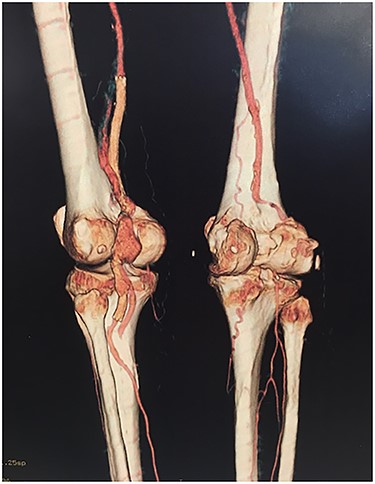

Approval for retrospective reports is not required by our institutional review board. This study is in accordance with the principles of the Declaration of Helsinki. A 77-year-old man with multiple comorbidities, including coronary vascular disease, hypertension, dyslipidemia, previous right carotid endarterectomy, and endovascular aortic repair (in 2011), was referred to our unit for evaluation of a retropopliteal pulsatile mass. He had undergone infra-popliteal stenting 18 months earlier, to treat peripheral arterial disease with severe left claudication. The procedure was performed at another vascular institute, and the stent type was unknown. Physical examination revealed the presence of a femoral and popliteal pulse and the absence of tibial pulses; at admission, the ankle–brachial index was 0.8. According to the patient, he had noticed the mass in the last 2 months prior to admission, but the absence of pain delayed his presentation to the hospital. An ultrasound scan was performed on admission and revealed a large popliteal pseudoaneurysm with normal flow present distally, and fracture of the stent was confirmed by computed tomography, which also detected a 4.2 cm dilatation of the left popliteal artery (Figs 1–3).

Angiotomography revealed fracture of a stent deployed in the popliteal artery and a pseudoaneurysm formation of size 4.2 cm at the part of stent fracture.